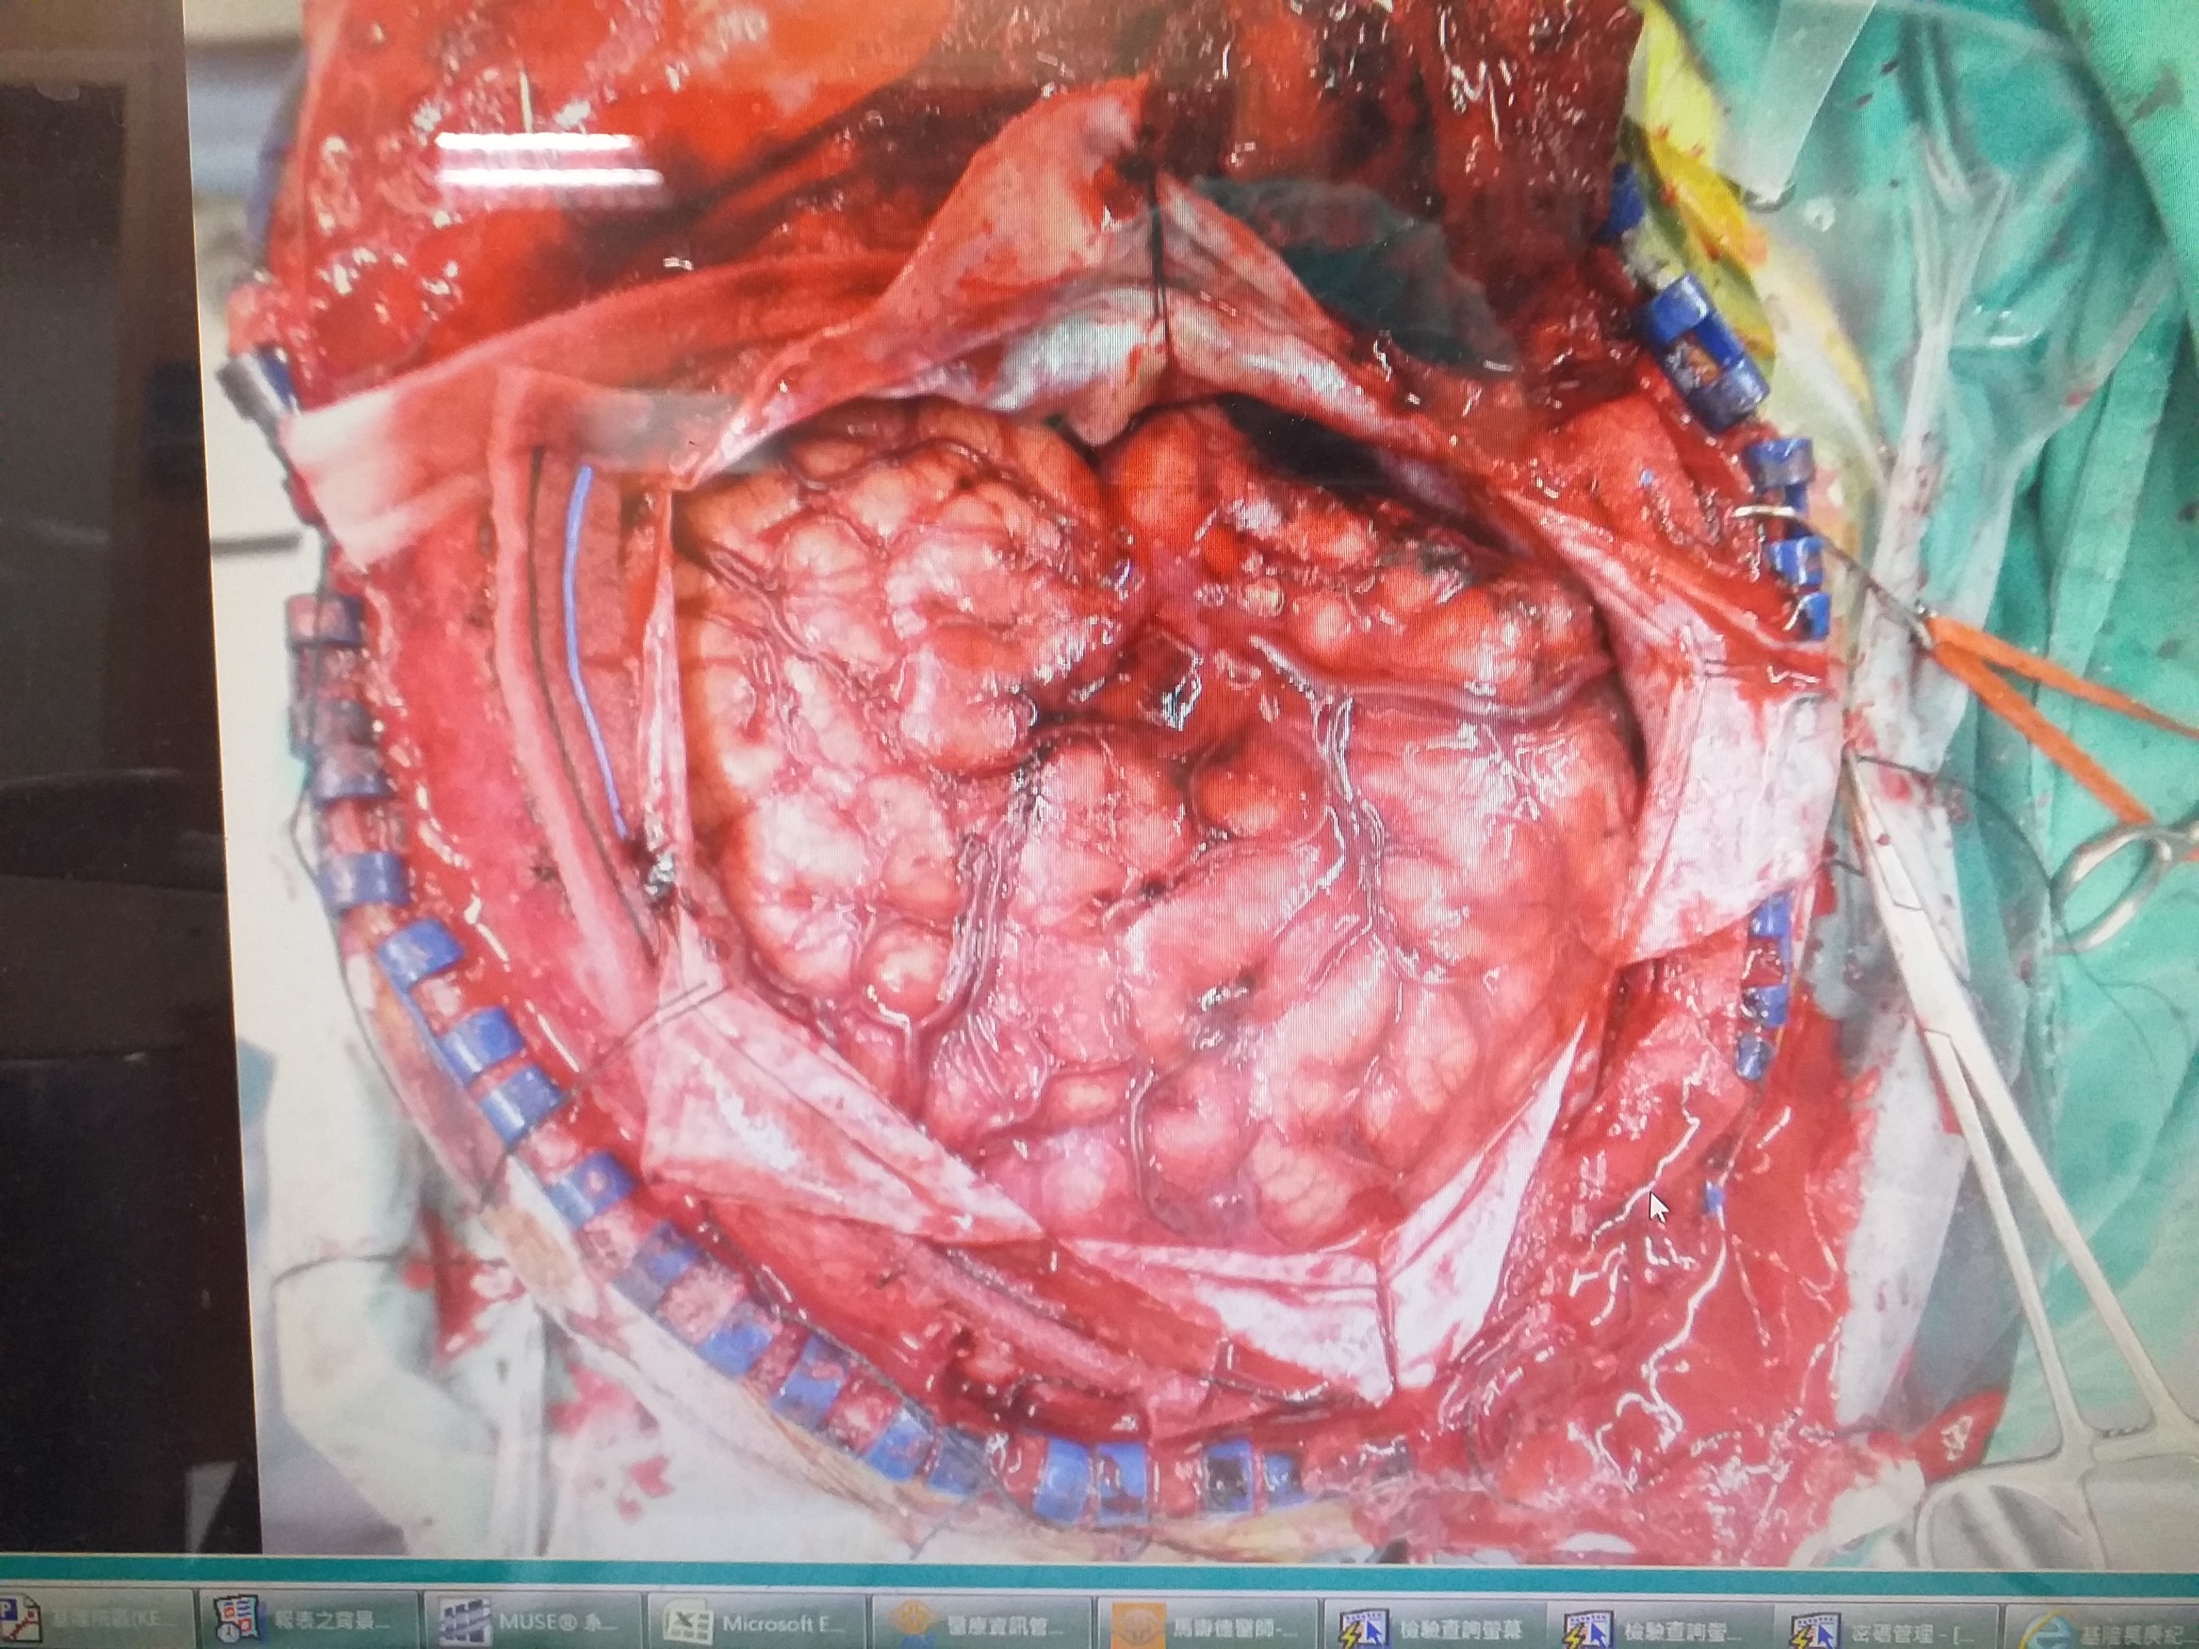

Traumatic brain injury in real world

image